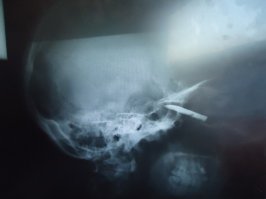

15 лет уже живу с пятисантиметровым осколком ножа в голове, под левым глазом. А жив только благодаря лицевому хирургу, отказавшемуся без дополнительного обследования делать срочную, вроде, на тот момент операцию. Уже потом после нескольких консилиумов, МРТ и разных множественных обследований его опасения подтвердились. Трогать осколок смертельно опасно. Настолько "удачно" он там засел. Как мне потом сказал Евгений Иванович (тот самый лицевой хирург), что рукавами моей "счастливой рубашки" можно смело несколько раз землю обернуть и ещё останется. Так и живём. )))